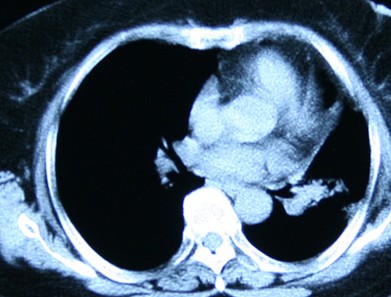

(2)B超检查:子宫明显增大,瘤体边界不规则,与肌层分界不清,其回声为均匀的低回声,或呈网格状蜂窝样强弱不均回声,类似葡萄胎。如有疑问可拨打热线电话:0755-82338559 。